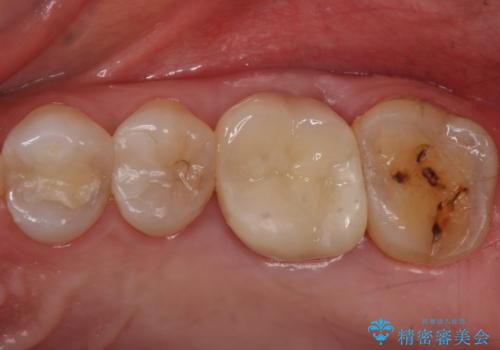

検査で見つかった虫歯 セラミッククラウンでの治療

担当医 岡田康成